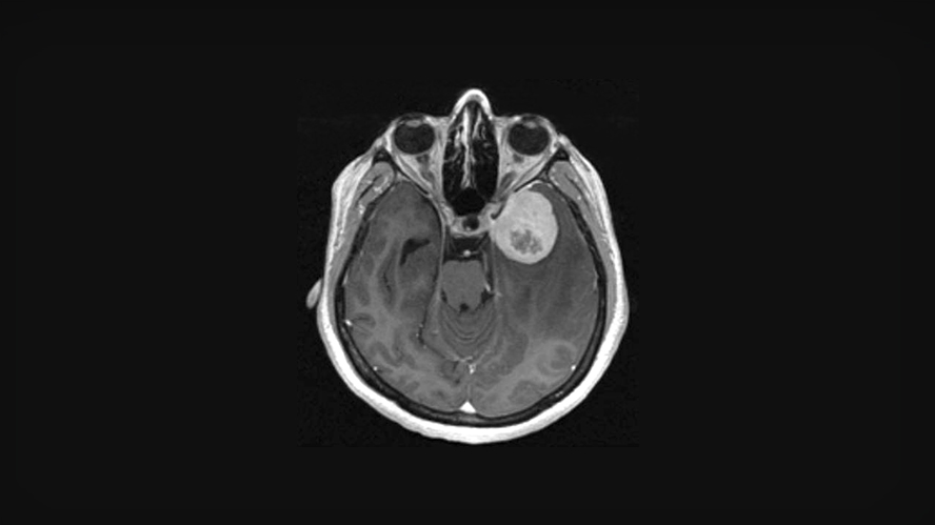

Although TERT promoter mutations are a recognized prognostic marker for meningiomas, their rarity limits their use. Overall TERT expression may be a more clinically relevant marker as it is more common. (Image provided by the research team)